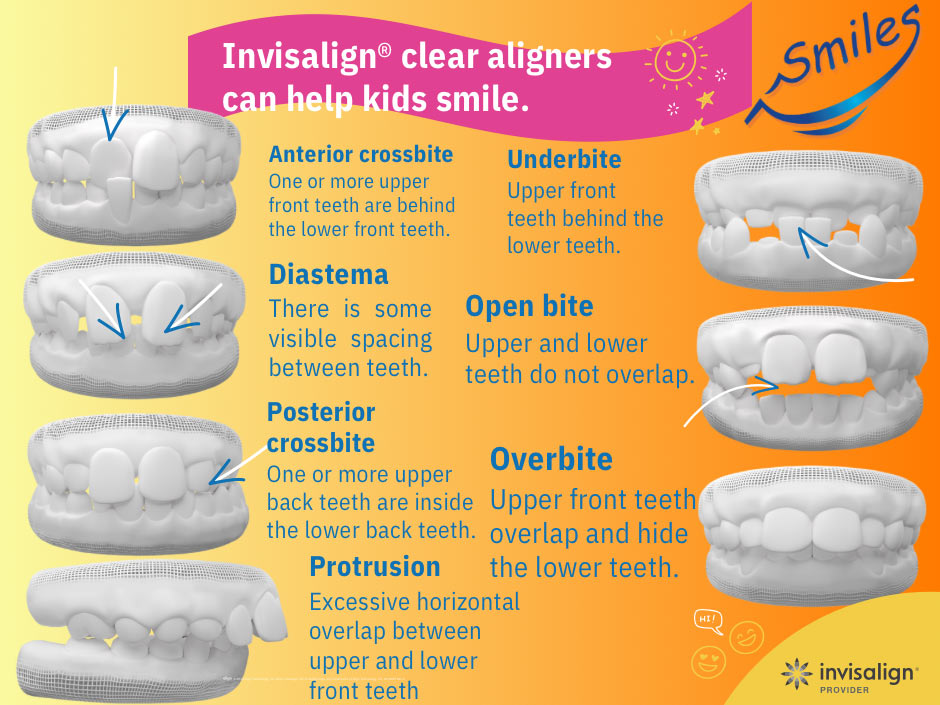

Orthodontics for kids involves more than just moving teeth. It includes dentofacial orthopedics, a term that translates to simultaneously guided dentition growth and facial bone growth. This early phase of orthodontics is the first of two phases of orthodontic care and starts when kids are well under 10 years of age. A big benefit to phase one orthodontics is that we can utilize the primary molars as appliance supports. Appliances for phase one orthodontics include palatal expanders and early clear aligners.